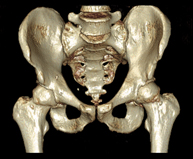

Exploració radiològica que mitjançant un sistema de raigs X i detectors que giren al voltant del pacient i que reconstrueixen les imatges per ordinador (TC Multidetector), permet l'estudi detallat dels ossos, els músculs i les articulacions de la mà i el canell. - TC de la pelvis òssia

Exploració radiològica que mitjançant un sistema de raigs X i detectors que giren al voltant del pacient i que reconstrueixen les imatges per ordinador (TC Multidetector), permet l'estudi detallat dels ossos, els músculs i les articulacions de la pelvis. - TC de malucs

Exploració radiològica que mitjançant un sistema de raigs X i detectors que giren al voltant del pacient i que reconstrueixen les imatges per ordinador (TC Multidetector), permet l'estudi detallat dels ossos, els músculs i les articulacions del maluc. - TC de sacroilíaques